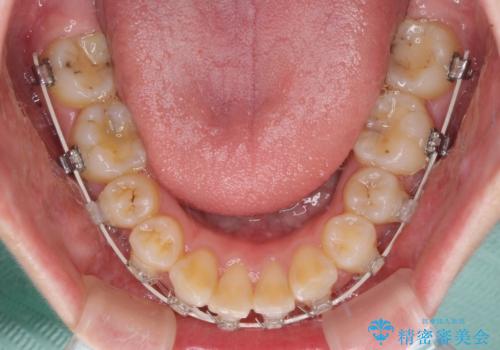

- 矯正装置

- 審美装置

上顎前突を改善するために上顎左右第一小臼歯を抜歯し、補助装置を用いて上顎臼歯が前方に移動しないように工夫しながら、表側のワイヤー装置にて歯列を整えていくこととしました。

予想通りに治療は困難を極め、その上途中来院されない時期があったため、非常に長期間に及びましたが、周囲の方々が驚愕するほど口元の印象を改善することができました。